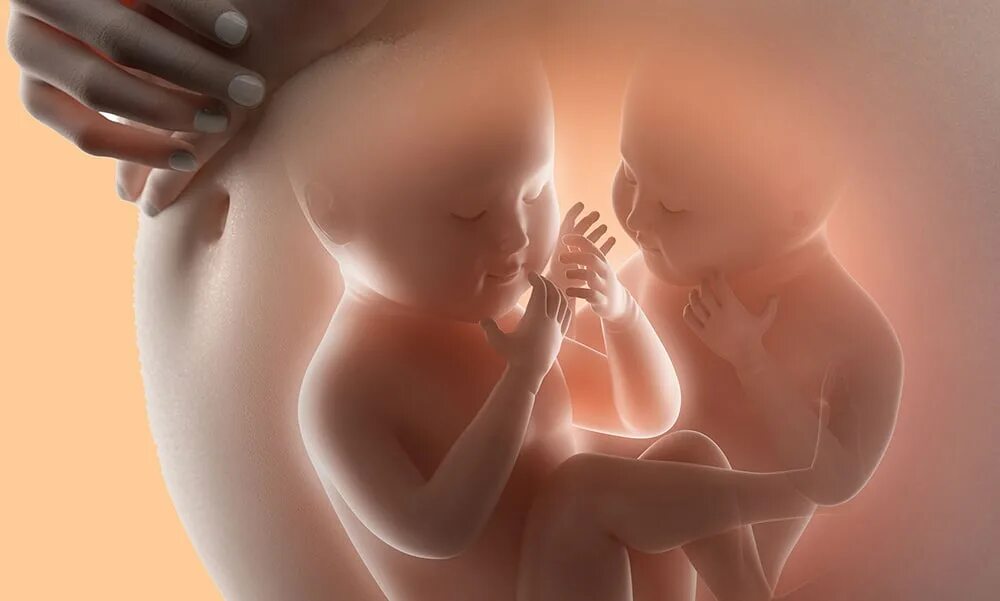

Эмбрион близнецов